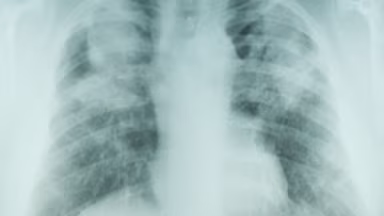

The pneumoconioses are typically detected through radiological imaging. Severity of lung impairment can be assessed using pulmonary function tests. The International Labor Office (ILO) provides guidelines for classifying radiographs of the pneumoconioses.

NIOSH operates the B Reader Program. This program allows physicians to document their proficiency in classifying radiographs (using ILO guidelines) by taking an examination.